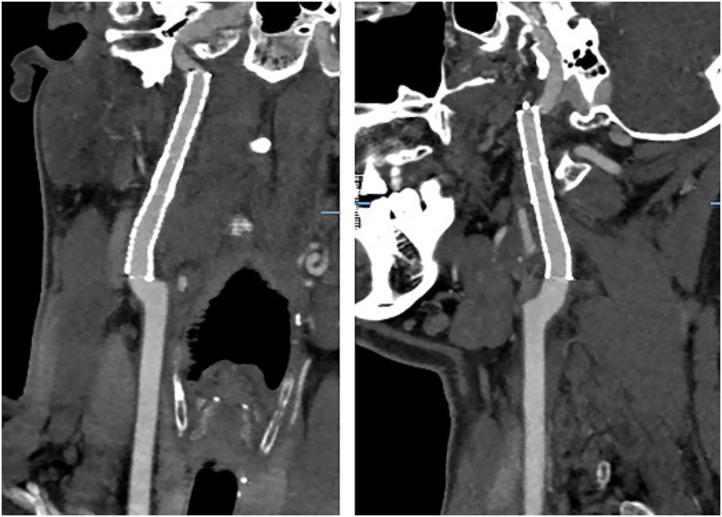

Internal carotid artery dissection (ICAD) results from a tear in the intima or rupture of the vasa vasorum with bleeding within the media resulting in separation of the vessel wall layers and a false lumen. It may cause arterial stenosis, occlusion, or dissecting pseudoaneurysm. Currently, the treatment of ICAD is controversial, including drug therapy and endovascular stent implantation. Simultaneous spontaneous dissection of bilateral carotid artery is rarely reported. We reported a 39-year-old-man with bilateral ICAD. Although the long-term durability of endovascular stent remains to be determined, for ICAD failed with active drug treatment and combined with hemodynamic impairment, early endovascular stent should be considered.

颈内动脉夹层(ICAD)是由于内膜撕裂或滋养血管破裂,血液在中膜内出血,导致血管壁各层分离并形成假腔。它可能导致动脉狭窄、闭塞或夹层假性动脉瘤。目前,ICAD的治疗存在争议,包括药物治疗和血管内支架植入。双侧颈动脉同时自发性夹层的报道很少。我们报告了一名39岁的双侧ICAD男性患者。尽管血管内支架的长期耐久性仍有待确定,但对于积极药物治疗失败且合并血流动力学损害的ICAD,应考虑早期进行血管内支架治疗。